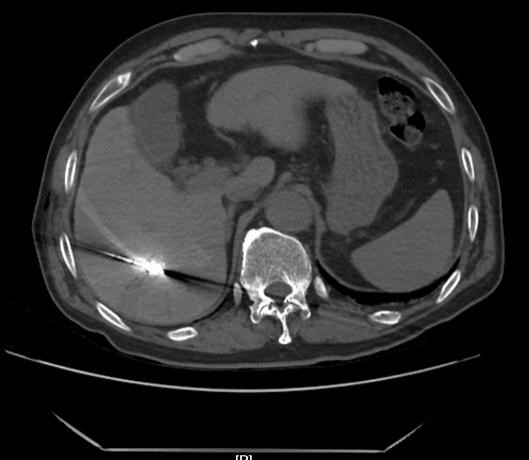

(消融前见肝脏病灶内碘油沉积良好)